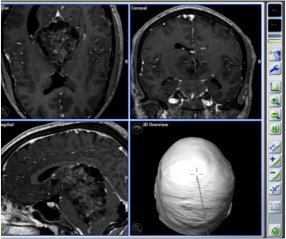

NEURONAVIGATION + IONM

Trans-sulcal Approach

Pre-operative

Post-operative